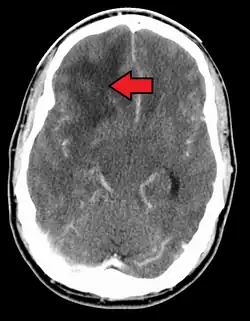

GBM in the frontal right lobe as seen on CT scan

When viewed with MRI, glioblastomas often appear as ring-enhancing lesions. The appearance is not specific, however, as other lesions such as abscess, metastasis, tumefactive multiple sclerosis, and other entities may have a similar appearance.[61] Definitive diagnosis of a suspected GBM on CT or MRI requires a stereotactic biopsy or a craniotomy with tumor resection and pathologic confirmation. Because the tumor grade is based upon the most malignant portion of the tumor, biopsy or subtotal tumor resection can result in undergrading of the lesion. Imaging of tumor blood flow using perfusion MRI and measuring tumor metabolite concentration with MR spectroscopy may add diagnostic value to standard MRI in select cases by showing increased relative cerebral blood volume and increased choline peak, respectively, but pathology remains the gold standard for diagnosis and molecular characterization.